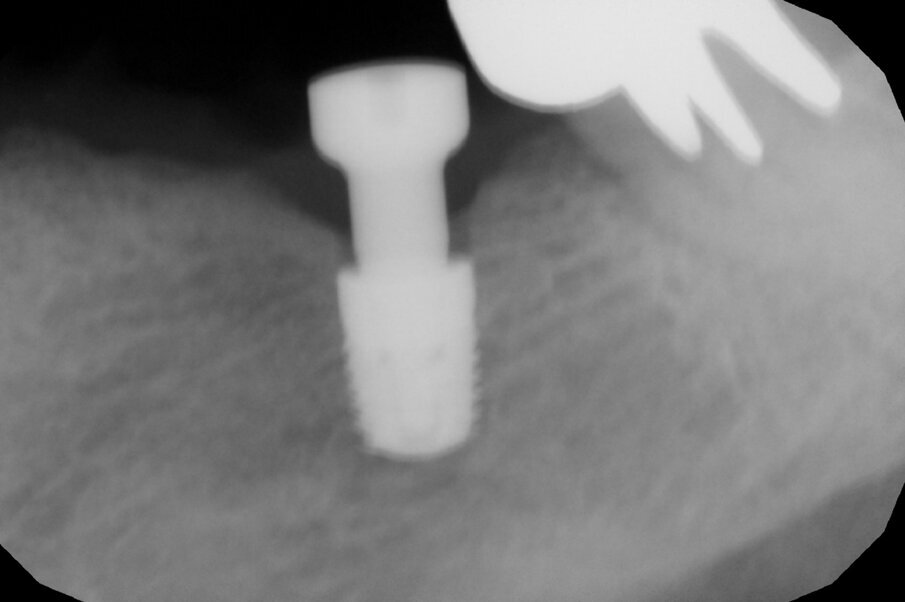

It was evident that tooth #34 had to be extracted. Despite the overload of tooth #37, the patient refused its extraction because it was not painful. We therefore proceeded with the separation of the existing bridge, maintaining the coverage of tooth #37 and the exposure of the edentulous part. Subsequently, the extraction of tooth #34 was performed. A CBCT assessment of the mandibular dental arch was performed, and the insertion of a 3.6 mm diameter and 9.0 mm long GTB implant in position #34 and of a 4.3 mm diameter and only 6.0 mm long GTB implant was planned (Fig. 2). This last choice was necessary not to avoid contact with the inferior alveolar nerve but because of the presence of a very high mylohyoid line and the consequent inclination of the lingual bone wall of the mandible below that line. We favoured the prosthetic axis of the implant rather than a greater length of the implant, which is obtainable by tilting it in a lingual–buccal direction. The surgical planning was performed according to the surgical protocol for GTB implants, which provides for the flattening of the knife blade ridge, the positioning of implants in the prosthetic axis and sinking the implant to the sub-crestal level of 1.5 mm. During surgery, we obtained an insertion torque of 25 Ncm in position #34 and of 20 Ncm in position #36 (Figs. 3a & b).